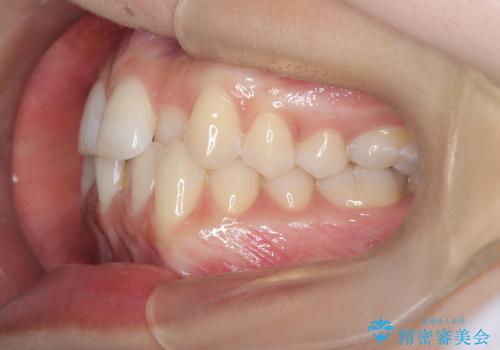

歯並びの乱れに加え、**反対咬合(上下のかみ合わせのズレ)**も認められたため、見た目だけでなく、かみ合わせの改善も同時に行っています。

治療後は歯並び・かみ合わせともに大きく改善し、患者様にも大変ご満足いただけました。